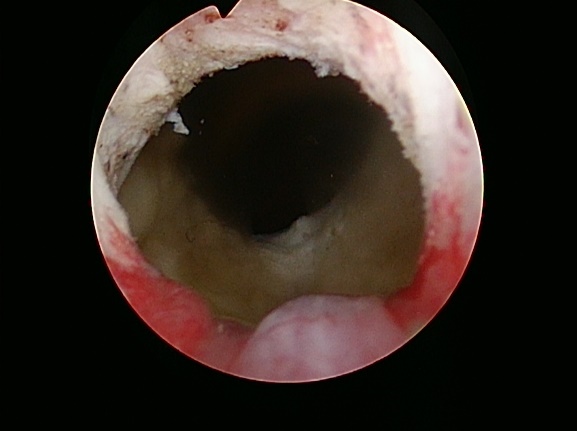

前立腺切除前

前立腺切除後